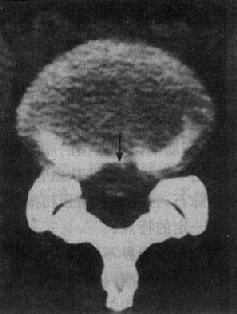

2.椎间盘脱出 CT表现为①椎管内前方出现脱出椎间盘的块影(图2-2-2),CT值低于骨但高于硬膜囊;②椎管和硬膜囊间的脂肪层消失,系最早出现变化;③神经根被推压移位;④硬膜囊受压变形(图2-2-2)。

图2-2-2 腰椎间盘中央型脱出(腰4~5)